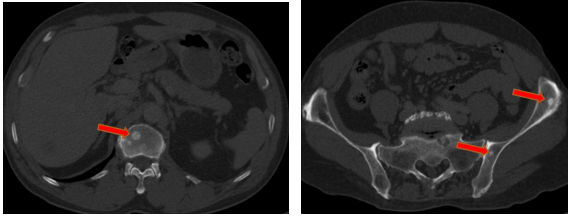

-         Chụp cắt lớp vi tính ổ bụng (08/2025): Nhu mô gan phải có vài nốt, nốt lớn nhất hạ phân thùy VII có nốt giảm tỷ trọng, ngấm thuốc kém sau tiêm đường kính 24mm, hạ phân thùy II, III có nốt 2 giảm tỷ trọng đường kính 13mm và 27mm. Các ổ đặc xương rải rác đốt sống ngực thắt lưng, xương cùng và xương chậu hai bên – theo dõi tổn thương thứ phát

Hình 04: Nhu mô gan phải có vài nốt, nốt lớn nhất hạ phân thùy VII có nốt giảm tỷ trọng, ngấm thuốc kém sau tiêm đường kính 24mm, hạ phân thùy II, III có nốt 2 giảm tỷ trọng đường kính 13mm và 27mm

Hình 05: Các ổ đặc xương rải rác đốt sống ngực thắt lưng, xương cùng và xương chậu hai bên – theo dõi tổn thương thứ phát

-         Chụp cắt lớp vi tính ổ bụng (11/2025): Nhu mô gan phải có vài nốt, nốt lớn nhất hạ phân thùy VII có nốt giảm tỷ trọng, ngấm thuốc kém sau tiêm đường kính 8mm, hạ phân thùy II, III có nốt giảm tỷ trọng đường kính (tổn thương giảm đáng kể so với phim chụp ngày 08/2025). Các ổ đặc xương rải rác đốt sống ngực thắt lưng, xương cùng và xương chậu hai bên.

Hình 11: Tổn thương ngấm thuốc kém nhu mô gan hạ phân thùy II giảm đáng kể kích thước

Hình 12: Tổn thương ngấm thuốc kém nhu mô gan hạ phân thùy VII giảm đáng kể kích thước

+      Các tổn thương ngấm thuốc kém do di căn tại gan giảm kích thước đáng kể (27mm còn 8mm)